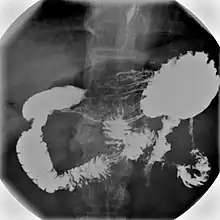

An upper gastrointestinal series, also called a barium swallow, barium study, or barium meal, is a series of radiographs used to examine the gastrointestinal tract for abnormalities. A contrast medium, usually a radiocontrast agent such as barium sulfate mixed with water, is ingested or instilled into the gastrointestinal tract, and X-rays are used to create radiographs of the regions of interest. The barium enhances the visibility of the relevant parts of the gastrointestinal tract by coating the inside wall of the tract and appearing white on the film. This in combination with other plain radiographs allows for the imaging of parts of the upper gastrointestinal tract such as the pharynx, larynx, esophagus, stomach, and small intestine such that the inside wall lining, size, shape, contour, and patency are visible to the examiner. With fluoroscopy, it is also possible to visualize the functional movement of examined organs such as swallowing, peristalsis, or sphincter closure. Depending on the organs to be examined, barium radiographs can be classified into "barium swallow", "barium meal", "barium follow-through", and "enteroclysis" ("small bowel enema"). To further enhance the quality of images, air or gas is sometimes introduced into the gastrointestinal tract in addition to barium, and this procedure is called double-contrast imaging. In this case the gas is referred to as the negative contrast medium. Traditionally the images produced with barium contrast are made with plain-film radiography, but computed tomography is also used in combination with barium contrast, in which case the procedure is called "CT enterography".[1]

Types

Various types of barium X-ray examinations are used to examine different parts of the gastrointestinal tract. These include barium swallow, barium meal, barium follow-through, and barium enema.[2] The barium swallow, barium meal, and barium follow-through are together also called an upper gastrointestinal series (or study), whereas the barium enema is called a lower gastrointestinal series (or study).[3] In upper gastrointestinal series examinations, the barium sulfate is mixed with water and swallowed orally, whereas in the lower gastrointestinal series (barium enema), the barium contrast agent is administered as an enema through a small tube inserted into the rectum.[2]

Medical uses

Barium X-ray examinations are useful tools for the study of appearance and function of the parts of the gastrointestinal tract. They are used to diagnose and monitor esophageal reflux, dysphagia, hiatus hernia, strictures, diverticula, pyloric stenosis, gastritis, enteritis, volvulus, varices, ulcers, tumors, and gastrointestinal dysmotility, as well as to detect foreign bodies.[3][6] Although barium X-ray examinations are increasingly being replaced by more modern techniques, such as computer tomography, magnetic resonance imaging, ultrasound imaging, endoscopy and capsule endoscopy,[7] barium contrast imaging remains in common use because it offers the advantages of greater affordability, wider availability,[1][5] and better resolution in assessing superficial mucosal lesions.[7][8]